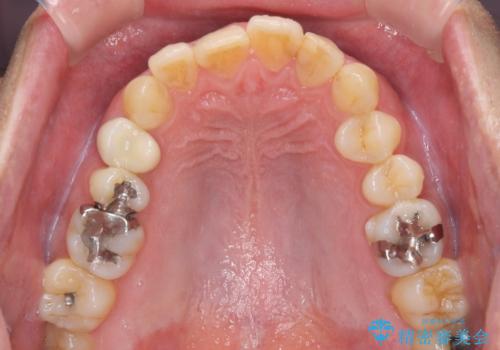

- 外に飛び出した側方の歯と、前歯のデコボコを気にして来院された患者様です。

IPR(歯と歯の間を削る)によってデコボコが解消するように設計し、インビザラインにより治療を行うこととしました。

治療途中で1年半以上通院されない時期があったため、後戻りが生じたことで治療期間が長くなってしまいました。

親知らずを抜去したことで、下顎のデコボコがきれいに解消されました。